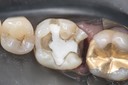

Matt Dodson #3 pre-op

Matt Dodson #3 caries removal